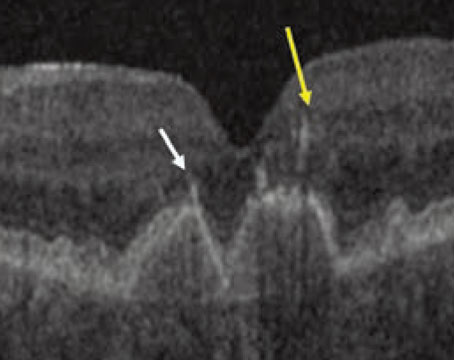

How imaging is advancing management of dry AMD

Emerging modalities and deep learning are helping to expose an old foe in non-neovascular age-related macular degeneration: reticular pseudodrusen.